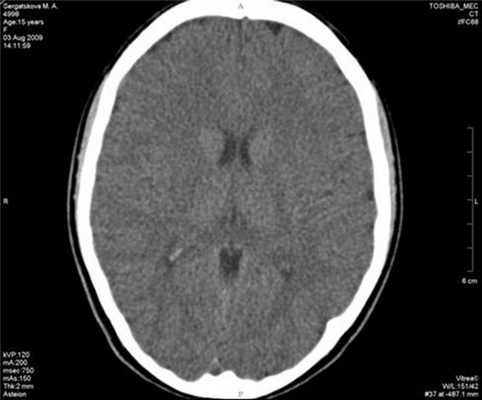

Общий, биохимический анализ крови и анализ мочи соответствуют возрастной норме. Педиатром патологии внутренних органов не выявлено. При КТ-исследовании головного мозга изменения очагового и диффузного характера отсутствуют, боковые желудочки мозга обычных размеров и конфигурации, асимметричны (D>S) в пределах нормы (рис. 5). Рисунок 5. Больная С., 15 лет. КТ головного мозга. На рентгенограммах грудного отдела позвоночника и костей таза патологических изменений не выявлено. МРТ пояснично-крестцового отдела также без патологии. Ортопедически подтверждается лишь эквино-варусная деформация правой стопы. Электронейромиографическое исследование патологии периферической нервной системы не зарегистрировало. Дуплексное исследование сосудов головы и шеи изменение кровотока не выявило.